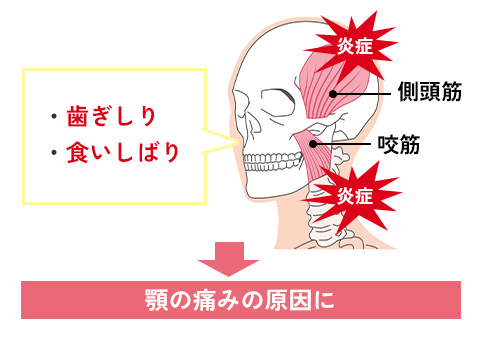

ブラキシズムと顎関節症

ブラキシズムとは、歯ぎしり・食いしばりなど顎の異常運動の総称です。ブラキシズムが長期間続くと、咬筋や側頭筋など咀嚼に関わる部位に炎症が起きて顎の痛みにつながると考えられています。

ブラキシズムは、お顔周りほぼ全ての器官に影響を与える恐れがあるため、早めの対処が必要です。原因としては噛み合わせ・ストレス・態癖など人によって様々で、それぞれ適切な治療を行っていきます。